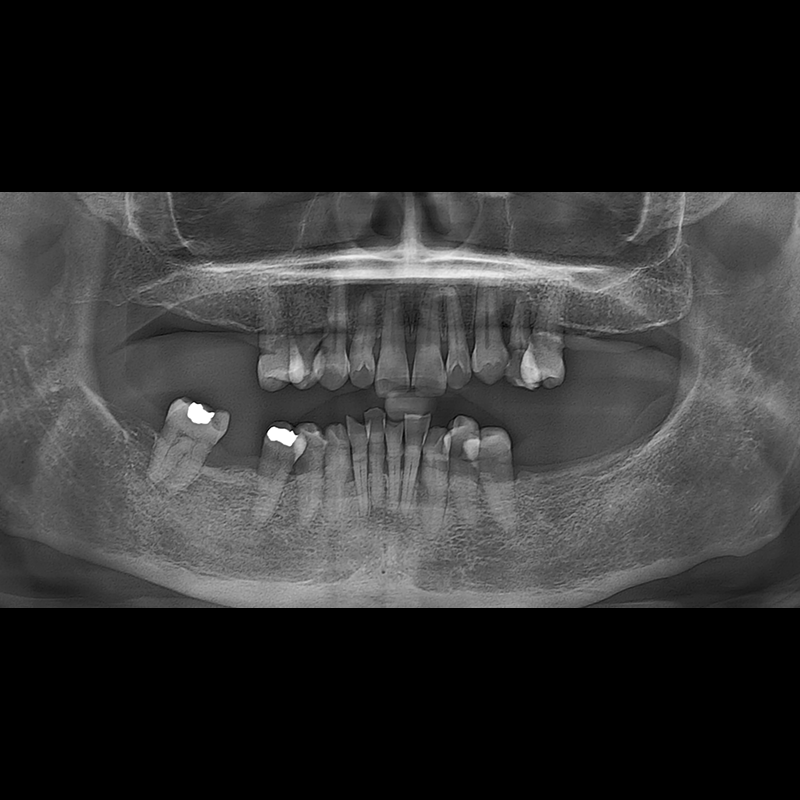

インプラント手術事例 2025.05.30

欠損した歯の部分と、生かしにくい歯の位置にインプラントを植立しました。